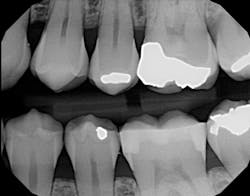

I used it on an elusive cracked tooth case. For once, I could actually see the fracture on an x-ray (figure 1). The noted distal fracture caused a great deal of biting pain for this patient. The one difference I noticed with All-Bond is its application method. Two coats are required and a scrubbing motion is needed during the two-coat process prior to curing. Yes, this is a little more time-consuming, but it did not bother me as much as I thought it might when I initially read the application directions. After I saw the results on the x-ray (figure 2), I knew the thin viscosity did not prohibit any type of condensed end product. The composite material flowed well into the proximal areas, and my patient left with no cracks in No. 19.

Figure 2: Restored cracked tooth x-ray